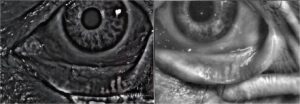

Regelmäßige Anordnung der Meibomdrüsen bei einem gesunden Patienten.

Die Meibographie zeigt den Ausfall des Drüsengewebes an.

Meibographie

Die Infrarotdarstellung der Meibomdrüsen ermöglicht eine Aussage zu diesem für einen funktionellen Tränenfilm äußerst wichtigen Gewebe. Weitere Therapien und die zukünftige Prognose leiten sich aus der Diagnostik ab.